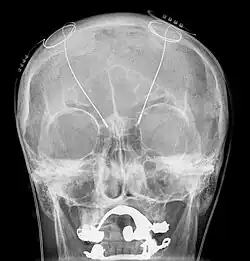

A working diagnosis is made from a neurological examination and evaluation. Parts of a complete examination include a physical examination, magnetic resonance imaging (MRI), patient history, and electrophysiological and accelerometric studies. A diagnosis of solely intention tremor can only be made if the tremor is of low frequency (below 5 Hz) and without the presence of any resting tremors.[1] Electrophysiological studies can be useful in determining frequency of the tremor, and accelerometric studies quantify tremor amplitude. MRI is used to locate damage to and degradation of the cerebellum that may be causing the intention tremor. Focal lesions such as neoplasms, tumors, hemorrhages, demyelination, or other damage may be causing dysfunction of the cerebellum and correspondingly the intention tremor.[14]

Deep brain stimulation treats intention tremors, but does not help related diseases or disorders such as dyssynergia and dysmetria.[17] Deep brain stimulation involves the implantation of a device called a neurostimulator, sometimes called a "brain pacemaker". It sends electrical impulses to specific parts of the brain, changing brain activity in a controlled manner. In the case of an intention tremor, the thalamic nuclear region is targeted for treatment. This form of treatment causes reversible changes and does not cause any permanent lesions. Since it is reversible, deep brain stimulation is considered fairly safe. Reduction in tremor amplitude is almost guaranteed and sometimes resolved. Some individuals have seen sustained benefits in MS progression.[18]